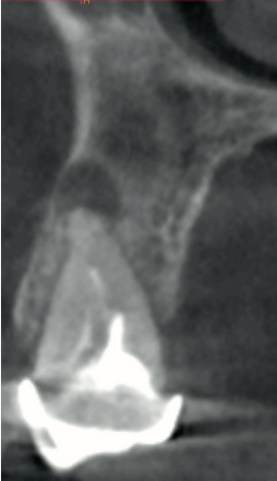

En la Historia Clínica no se evidenciaron antecedentes médico-quirúrgicos de interés, alergias medicamentosas conocidas ni hábitos nocivos. En la exploración intraoral, se apreció un implante en la localización del 1.6, con un pilar de cicatrización, y el diente 1.5 con un ferrule insuficiente para ser restaurado (Figura 1). En la exploración radiográfica, mediante escáner de haz cónico (CBCT), se apreció un tratamiento de conductos en el 1.5, así como una imagen radiolúcida a nivel apical (Figura 2). Se planificó la exodoncia del 1.5, para lo que se firmó previamente el consentimiento informado. Tras el mismo, se realizó un bloqueo anestésico mediante articaína al 4% con adrenalina 1:100.000 del nervio alveolar superior posterior y medio y el nervio palatino anterior. Se realizó la extracción de la forma más atraumática posible y se eliminaron del diente el cálculo y los restos de obturaciones con fresa de diamante de turbina (Dentsply Maillefer, Ballaigues, Suiza). Se pulió la superficie radicular con fresas de diamante de turbina con abundante irrigación, eliminando de esta forma el ligamento periodontal. El material de relleno endodóntico fue retirado usando fresas de Gates Glidden® (Dentsply Sirona Inc, Delaware, Estados Unidos) (Figura 3). Se cortó el diente en fragmentos ≤ 5 mm y se colocaron secos dentro del molino del dispositivo Tooth Transformer® (S.R.L, Milan, Italia) como indica el fabricante.

Tras la preparación del injerto, se procedió a su colocación en el alveolo del 1.5, usándose para cubrir el injerto una esponja hemostática (Proclinic, Madrid, España) y se suturó mediante un punto simple y un punto colchonero horizontal con sutura no reabsorbible de 4/0 (Supramid®, B. Braun, Barcelona, España), realizando una radiografía periapical paralelizada en el postoperatorio inmediato, así como un CBCT, para verificar la colocación adecuada del biomaterial en el alveolo post-extracción (Figuras 5 y 6).

A los 15 días se retiraron los puntos de sutura, apreciándose un buen aspecto de los tejidos blandos y la presencia de fibrina sellando la herida (Figura 7). Tras tres meses de cicatrización se comprobó su evolución mediante CBCT, apreciándose el mantenimiento de las dimensiones óseas en comparación con el escáner realizado antes de la extracción (Figura 8).